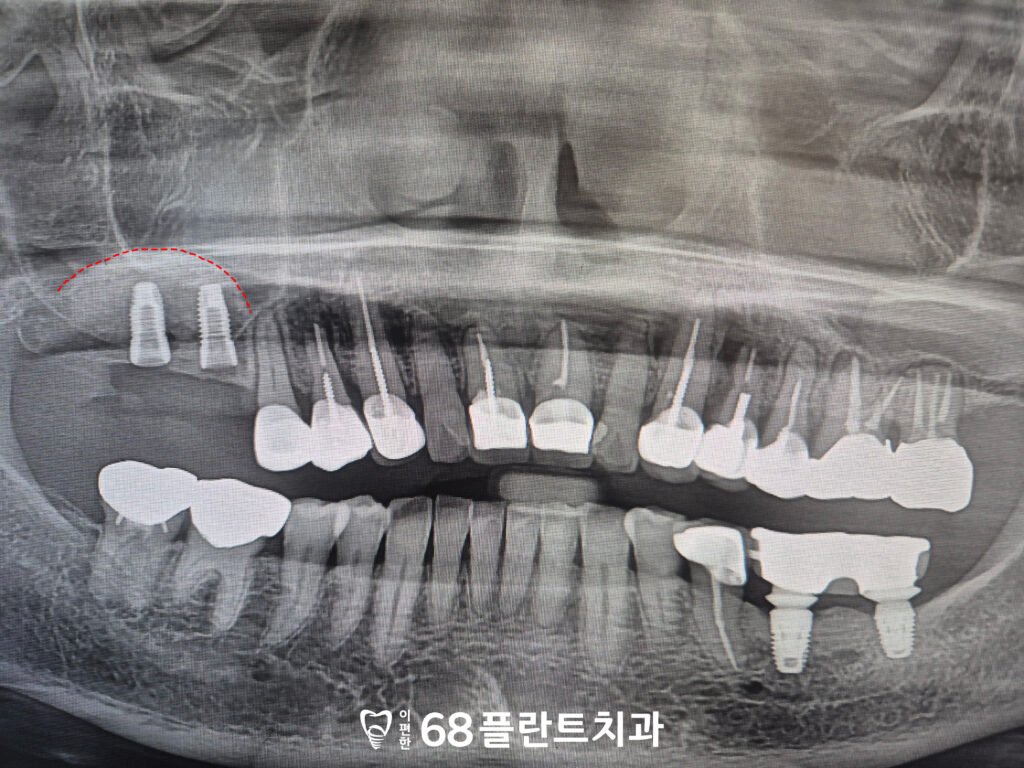

먼저 상악동거상술을 진행하여

부족한 뼈를 보강한 후,

임플란트를 식립할 수 있는

안정적인 환경을 마련했습니다.

상악동의 천장을 들어 올려

인공 뼈를 채우는 방식을

진행하였습니다.

이후 임플란트도

같이 식립하였습니다.

상악동거상술을 통해

충분한 뼈를 확보한 후,

안정적인 환경이 마련되었기 때문에

임플란트를 바로 식립할 수 있었습니다.

이후 이식한 뼈와 임플란트의

치유기간을 기다렸습니다.